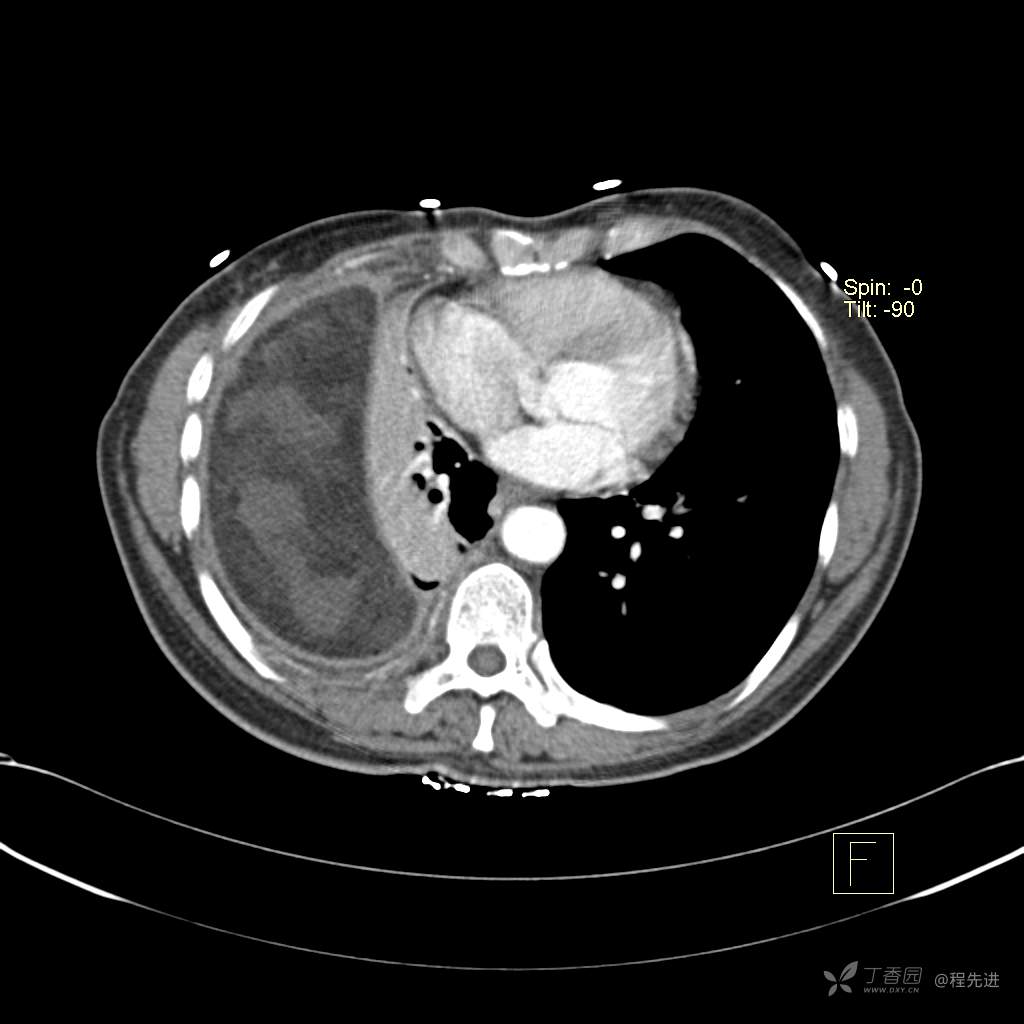

患者性别:女

患者年龄:51岁

简要病史:胸闷半年